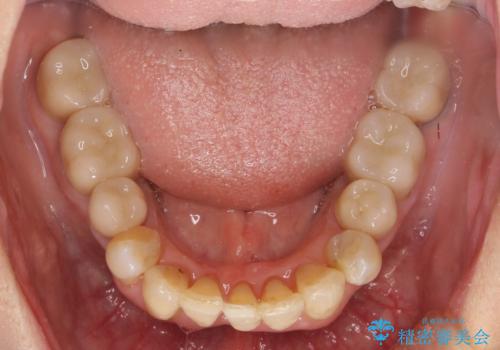

- 前歯の見た目・歯並び・銀歯の見た目の改善を求めて来院されました。

まずガタ付きの強い歯並びをマウスピース矯正インビザラインで整えたのち、セラミック治療による審美性の改善を計画します。

矯正治療が終わったのちに、精度の高いセラミックを装着することでより安定した噛み合わせとなり審美性も兼ね備えた口腔内状態で治療を終了し、今後のメンテナンスを行っていくことができます。